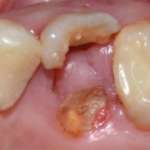

Impianti immediati post-estrattivi in siti infetti con ausilio del laser Er,Cr: YSGG (2.780nm) Premium

Viene illustrata la tecnica di implantologia immediata associata alla disinfezione laser e presentato un caso clinico, con follow-up a 5 anni, per chiarire i passaggi principali per una corretta gestione della procedura. Il laser Er,Cr:YSGG 2.780nm può, infatti, ridurre in modo significativo la concentrazione batterica presente nell’alveolo di un dente estratto.